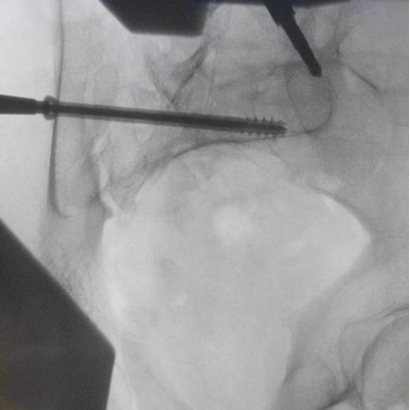

據(jù)了解,患者37歲,為高墜傷患者,入院合并顱腦挫傷、盆腔臟器出血、骨盆骨折多發(fā)傷患者。為最大限度降低手術(shù)風(fēng)險(xiǎn),同時(shí)給予患者滿(mǎn)意的手術(shù)療效,術(shù)前綜合評(píng)估患者病情,擬定行“天璣機(jī)器人”輔助定位下骨盆骨折微創(chuàng)手術(shù)。2月13日10時(shí),手術(shù)正式開(kāi)始。拉薩市人民醫(yī)院采集患者術(shù)中二維影像,通過(guò)骨科手術(shù)機(jī)器人擬定螺釘打入位置方向后,吳宏華主任完成手術(shù)設(shè)計(jì),成功為該患者置入了一顆高難度骶髂螺釘,出血5ml,切口1cm。術(shù)后圖像顯示,螺釘位置及方向完全符合手術(shù)規(guī)劃,沒(méi)有一絲偏差,手術(shù)最終獲得圓滿(mǎn)成功。

圖為透視下見(jiàn)置入的骶髂螺釘,位置、長(zhǎng)度精準(zhǔn),無(wú)絲毫偏差